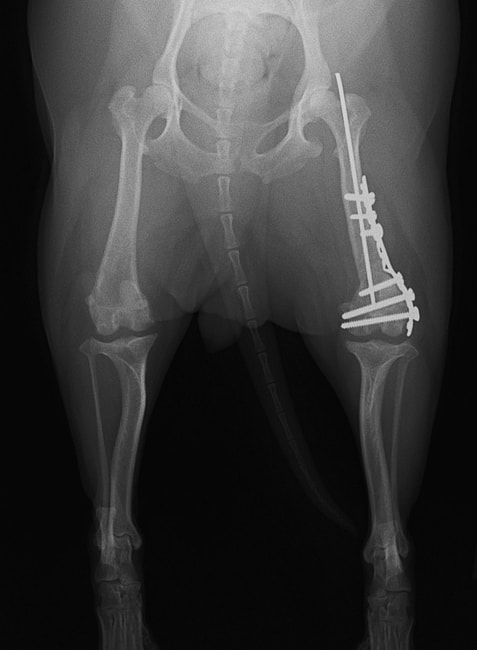

■ 症例24 キャバリア 7か月

左右膝蓋骨内方脱臼(左:グレードⅣ 右:グレードⅢ)

以前から左右後肢の跛行が認められ、整形外科学的検査・レントゲン検査により左右の膝蓋骨脱臼が認められた。症状が重度である左膝の膝蓋骨脱臼整復術を行った。外科手技は縫工筋及び内側広筋の解放、脛骨粗面の外側転位、滑車ブロック形造溝術、内外側関節方の縫縮を実施した。術後一か月時点で、左の膝蓋骨は安定しており経過は良好である。

本症例は成長期における重度の膝蓋骨脱臼であり、術後の再発の可能性もあるため、経過をしっかりと観察していく必要がある。また、今回手術を実施していない右膝に関しても経過を観察し、手術を検討していくこととする。